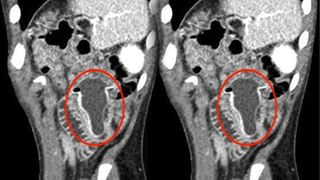

పరిశోధనల ప్రకారం.. పుర్రెకు ట్రెపనేషన్ అనే ప్రక్రియ జరిగిందని.. పుర్రె ముక్కను డ్రిల్లింగ్ చేయడం లేదా స్క్రాప్ చేయడం ద్వారా పుర్రెలో రంధ్రం ఏర్పడేలా చేశారన్నారు. సాధారణంగా తలనొప్పి తగ్గించడానికి లేదా మూర్ఛ వంటి పరిస్థితులకు చికిత్స చేయడానికి ఇలా చేస్తారట. ఎందుకంటే.. ఆ కాలంలో ఇది దుష్టశక్తులు దరి చేరకుండా చేస్తుందని నమ్మేవారు. ట్రెపనేషన్ అనేది అప్పటి ఆచారంగా భావిస్తున్నారు శాస్త్రవేత్తలు. కాగా, ప్రస్తుతం ఈ పుర్రె స్విట్జర్లాండ్లోని లౌసాన్ కాంటోనల్ మ్యూజియం ఆఫ్ ఆర్కియాలజీ అండ్ హిస్టరీలో ఉందని.. ప్రజలు సందర్శనార్ధం పొందుపరిచారన్నారు.